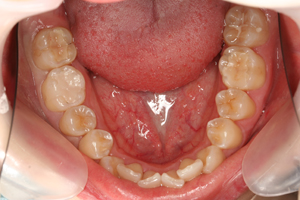

セット後

これで健康的な口元になり、大きく口を開けて笑った写真も気になりません。